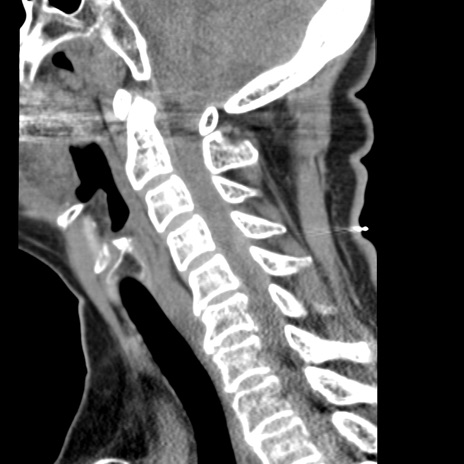

症例50 頚椎CT(矢状断像)

【症例】60歳代女性

【主訴】後頭部〜右後頸部にかけての痛み

【現病歴】本日飲食店でコーヒーを飲んでいたところ、突然後頭部〜右後頸部にかけて痛みが出現し、右上肢の感覚障害を伴ったため救急要請。

【身体所見】脳神経学的に明らかな異常所見を認めず。右上肢に軽度の感覚障害あり。

異常所見と診断は?

頚椎CT